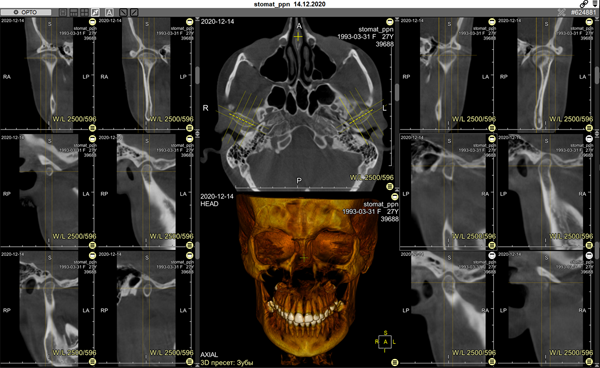

The program is presented in 5 viewing modes:

1 Mode

- axial scan, orthopantomogram, dental cross-sections, and 3D model, opens by default

Designed for correcting the reference curve and detailed examination of teeth and jaws

Allows analyzing skeletal symmetry, identifying unerupted and supernumerary teeth, and accurately identifying root resorption and orientation, etc.

2 Mode

– cephalometric analysis (orthopantomogram and MIP)

3 Mode

- standard 3 MPR projections and 3D model

Allows analyzing the facial skeleton

It has full functionality for managing volumes in CT

Projections: oblique, curved, MIP, MinIP, and Average

Arbitrary volume rotations, synchronization of manipulations across all projections

- temporomandibular joint (TMJ) analysis

Allows analyzing TMJs

Creates 2 projections parallel to the long axis of the condylar head and 4 perpendicular projections, allowing full assessment of the condition of both TMJs and their comparison